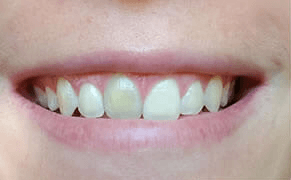

Cas clinique « SMILE RED FLAG MEI » : Traitement de remplacement d’une dent du sourire par un implant en Mise en Esthétique Immédiate. Visualisation de la version définitve de la couronne sur implant avec un cosmétique en céramique.

Après la guérison des tissus mous (gencive) et durs (os alvéolaire), la couronne céramique esthétique a été installée sur l’implant.

Le maintien de l’esthétique du sourire dépend en grande partie de la reconstruction des tissus gingivaux entourant la couronne céramique esthétique et de l’os autour de l’implant.

Cicatrisation des tissus et résultat clinique à la pose de la couronne céramique